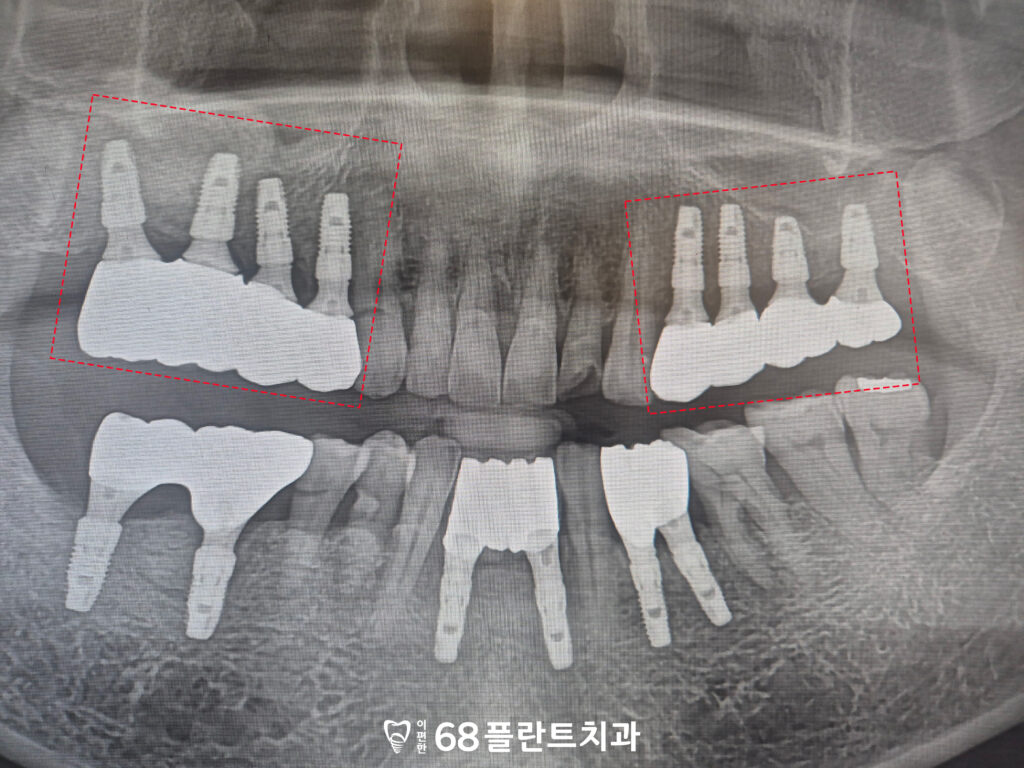

이후 특별한 문제 없이

치유 과정을 안정적으로 거쳤으며,

잇몸과 임플란트의 상태를 확인한 뒤

보철 작업을 진행하였습니다.

보철물 장착 후에는

교합과 기능을 점검하여

일상적인 식사와 저작이

무리 없이 이루어질 수 있도록

마무리하였습니다.

◆ 전 > 후 ◆

치료 마무리 후 사진입니다.

환자분께서는 치아 상실로 인해

식사가 불편하고 어려웠으나,

치료가 마무리된 현재는 임플란트가

안정적으로 자리 잡아

고기와 같은 음식도 무리 없이 씹을 수 있게 되었으며,

전반적인 저작 기능 회복에 대해

만족감을 표현해 주셨습니다.